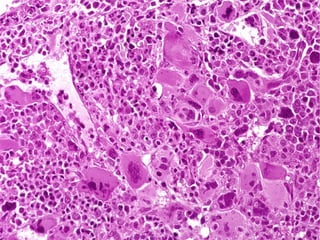

• #58 In AMML, M4, many of the peripheral leukemic cells look like monocytes, while in M5, Acute Monocytic Leukemia, MOST of them look like monocytes. M5 has also been called “Schilling”-type leukemia. (NOT the same Schilling of the B12 Schilling test)

• #59 In M6, many of the cells may resemble erythroid cells, in M7, many of the cells may resemble megakaryocytes. But in reality you would probably never think the blasts of M7 are related to megakaryocytes.